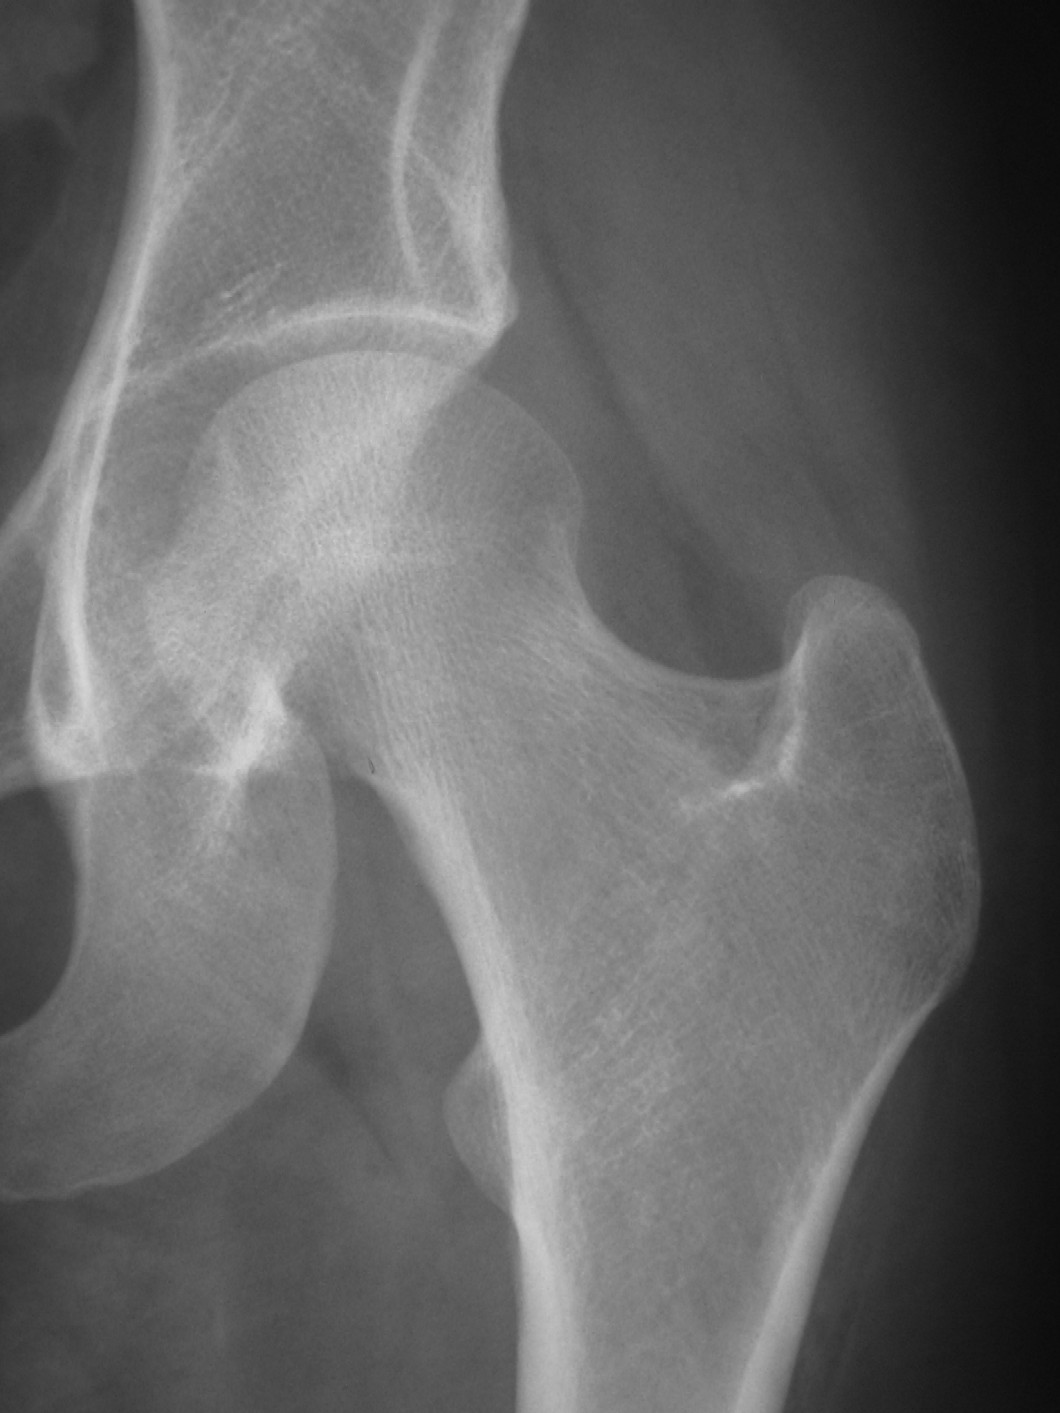

Note di coxa-artrosi bilaterale rappresentate da sclerosi dei tetti acetabolari con produzione osteofitosica e lieve riduzione asimmetrica delle interlinee articolari. 05.02.2016 13:31. Ho 48 anni e da una recente radiografia sono emersi segni di coxoartrosi bilateralmente con evidenza di sclerosi dei tetti acetabolari e di una discreta prominenza dei cigli cotiolidei. Regolare l' interlinea articolare e la morfologia di entrambe le teste femorali e non alterazione osteo -strutturali.

La coxartrosi è una malattia infiammatoria cronica che colpisce l'anca, provocata dall'usura della cartilagine presente all'interno dell'articolazione. Il danneggiamento della cartilagine riduce lo spazio protettivo presente tra le ossa, facendole sfregare l'una con l'altra e provocando la formazione di osteofiti, cioè speroni di.. Salve, 56 anni, donna, dolore inguine e gluteo. Rx riscontra note artrosiche al tratto lombare inferiore con spazio discale l5-s1 ridotto. Sclerosi artrosica dei tetti acetabolari. RIME articolari conservate. La terapia conservativa è efficace nel mio caso ai fini di rimandare/evitare intervento di protesi? grazie